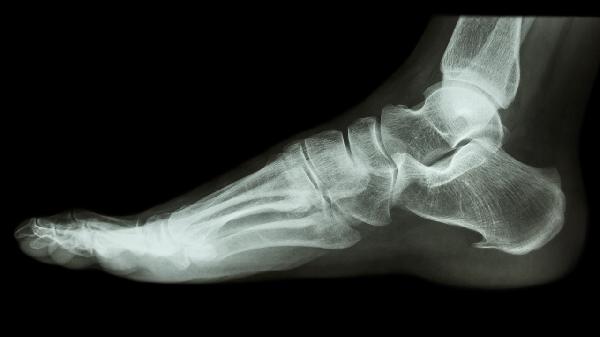

愈合期间应保持每日摄入300ml牛奶或等量乳制品,每周食用2-3次深海鱼类补充Omega-3脂肪酸。可进行上肢阻抗训练维持心肺功能,避免久坐导致静脉血栓。睡眠时双腿间夹枕头保持髋关节中立位,定期复查X线观察骨痂生长情况。戒烟限酒避免影响骨骼血供,控制体重减轻关节负担。